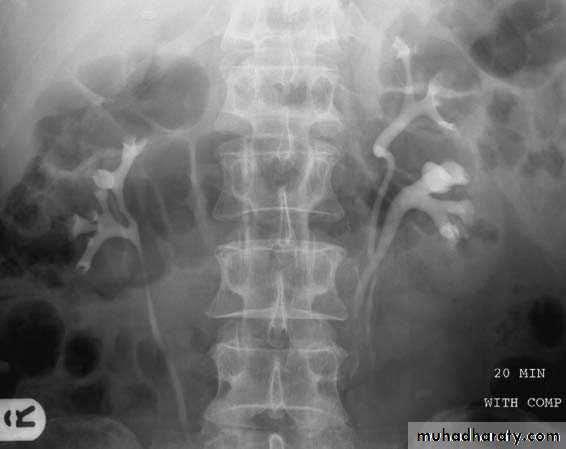

Normal IVU

pyelogram